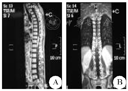

Enhanced sagittal and coronal MR imaging of the schwannoma

A:矢状位,B:冠状位

MRI是诊断椎管内占位病变的有效手段,因而不难区分髓内和髓外肿瘤,但髓内神经鞘瘤却没有特异性征象。目前,有关髓内神经鞘瘤影像学表现的报道较少,而且部分病例的MRI资料不全,多数学者认为髓内神经鞘瘤具有髓外硬膜内神经鞘瘤相似的影像学表现。一般来说,髓内神经鞘瘤MRI表现为T1WI等或稍低信号,T2WI等或稍高信号,多与脊髓界限清晰,可伴有脊髓空洞、水肿或囊变,注药增强扫描后可见肿瘤实质明显均匀强化且边界清晰[10]。本例肿瘤实质为稍低T1、高T2信号,其内可见明显的囊变区,增强后肿瘤实质部分强化明显均匀,边界清楚,且继发有脊髓空洞,这些表现虽与神经鞘瘤的典型征象相一致,但由于髓内神经鞘瘤发病率极低,故容易导致误诊。因此,结合此次诊疗经验,当MRI检查显示髓内病变显著强化、边界光滑清晰时应想到神经鞘瘤的可能。钱银峰等[11]总结以下征象有助于神经鞘瘤的诊断:(1)肿块以等或稍长T1、等或长T2信号为主,常伴有囊变;(2)增强后实质部分明显强化,且强化较均匀;(3)增强后肿瘤边界消楚;(4)肿瘤多较小,常不超过3个椎体节段;(5)肿瘤相连髓外神经根增粗(具有特征性,但较少见)。Kim等[12]认为瘤周水肿轻微是其特征之一。本组瘤周水肿较轻微,符合其特征性表现,但本组患者肿瘤较大,跨位T9~L1,提示肿瘤大小无明显诊断特异性。